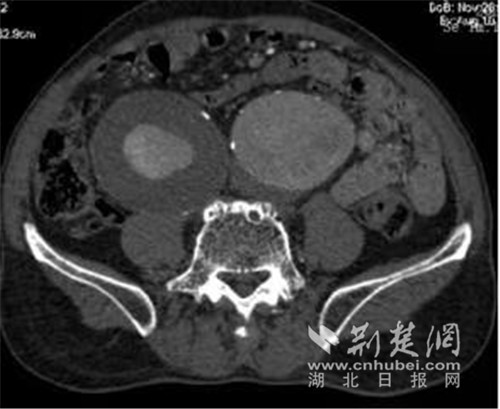

患者双侧髂总动脉巨大动脉瘤。通讯员供图

邓宏平介绍,由于陈先生主动脉瘤瘤颈扭曲严重、合并双侧巨大髂总动脉瘤、双侧巨大髂内动脉瘤,要根治此病,外科开放手术范围广、创伤大。常规微创手术技术复杂存在臀肌、肠道缺血坏死及生殖动脉、下肢动脉缺血风险。而腔内手术既要完全隔绝动脉瘤、又要保留至少一侧髂内动脉,需要周密的手术计划和娴熟的腔内手术技巧。